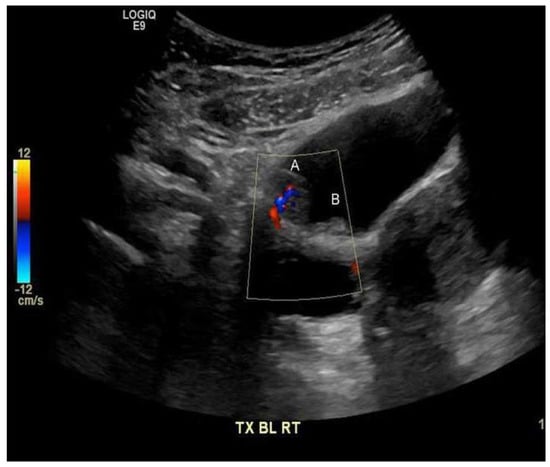

The urinalysis demonstrated a mild increase in the 21–50 red blood cells (20–50/HPF) and white blood cells (11–20 white blood cells/HPF). The urine cytology did not reveal any tumor cells, and the microscopic examination of the urine did not demonstrate any ova or parasites. Nitrites were not observed, and no growth was observed in the urine culture. The complete blood count revealed a white blood cell count of 5.7 × 109/L (range 4.5–11 × 109/L), hemoglobin 132 g/L (range 120–160 g/L), and platelets 381 × 109/L (range 140–440 × 109/L). The differential white blood cell count was normal, except for mild eosinophilia, with 1.15 × 109/L (range 0.0–0.4 × 109/L), or 18.0% (range 0.0–5.0%). The blood chemistry levels were all within normal ranges. A computerized axial tomographic scan (CT) of the abdomen and pelvis was performed and showed no pathologically enlarged lymph nodes. However, it revealed a 1.5 by 1.5 by 0.9 cm pedunculated intraluminal urinary bladder mass on the right side. The interpreting radiologist suggested that the mass could be better assessed by an ultrasound, which is shown in Figure 1. Although the ultrasound showed no stone, it raised concerns regarding possible bladder neoplasia. The patient underwent a cystoscopy with a transurethral resection of the mass for a histological assessment. The microscopic examination, as shown in Figure 2, revealed organisms that were morphologically compatible with the eggs of S. haematobium. We prescribed the patient 1200 mg of praziquantel orally every 12 h for one day (two doses). The one-month post-treatment follow-up included monitoring for eosinophilia and a microscopic examination of the urine (S. haematobium), which revealed a normal reading that confirmed that the patient had been cured.

Figure 1. Polypoid lesion along the right anterior superior wall of the urinary bladder (A) 1.5 by 1.5 by 0.9 cm, with the internal flow on the color Doppler imaging suggesting that the mass has a blood flow. Medially, a smaller adjacent polypoid lesion (B) measuring 0.9 cm is noted.